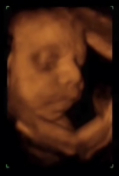

Séptimo mes: Desarrollo fetal

El feto mide algo menos de 40 centímetros y pesa alrededor de 1200 gramos a las 28 semanas. Este mes es en el que más vas a notar sus movimientos, dado su considerable tamaño y que todavía tiene sitio para realizar algunos movimientos amplios. A partir del próximo mes el feto disminuirá dr...